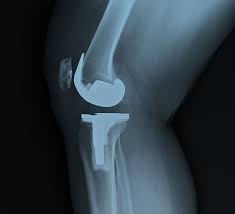

Several types of joint replacement surgeries are performed at low cost in Chandrapur. These include total knee replacement, total hip replacement, partial joint replacement, and revision surgeries. The choice of surgery depends on the patient’s age, activity level, joint condition, and overall health.

Standardized procedures in PMJAY-approved hospitals ensure predictable outcomes and minimize complications. As a result, patients regain mobility and enjoy improved joint function after low-cost surgery.

During joint replacement, damaged joint surfaces are replaced with durable implants, restoring smooth movement and reducing pain. Post-surgery, patients start physiotherapy to regain strength, flexibility, and balance. Low-cost joint replacement hospitals in Chandrapur prioritize early rehabilitation to achieve better long-term outcomes and improved independence.